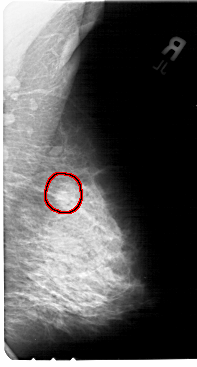

A_1397_1.LEFT_MLO

LEFT_MLO LINES 5491 PIXELS_PER_LINE 2926 BITS_PER_PIXEL 12 RESOLUTION 43.5 OVERLAY

FILE: A_1397_1.LEFT_MLO.OVERLAY

TOTAL_ABNORMALITIES 1

ABNORMALITY 1

LESION_TYPE MASS SHAPE LOBULATED MARGINS OBSCURED

ASSESSMENT 4

SUBTLETY 3

PATHOLOGY BENIGN

TOTAL_OUTLINES 1

BOUNDARY